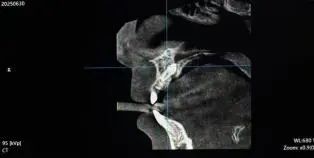

近日,一名家长来到我院口腔科,表示7岁孩子在换牙期间,门牙间隙过大,寻求治疗。通过CBCT(口腔颌面锥形束CT)影像检查,医生找到了一颗“埋伏”于上颌鄂侧(腭侧)骨内的多生牙。

术前影像检查

这颗多生牙位置刁钻,一是深度“埋伏”,完全埋藏在颌骨内,处于正常牙列上方深处,常规检查难以发现;二是临近要害,紧贴关键的鼻腭神经血管束,鼻腭神经血管束是上颌前部重要的感觉神经和供血通道,一旦术中损伤,或将造成上腭前部长期麻木、感觉异常,甚至影响局部血供;三是操作空间狭小,患儿口腔空间有限,加之患牙位置深,手术视野和器械操作面临不便。

科主任侯少慧术前充分评估后,制定了科学方案,凭借丰富经验与先进的CBCT三维定位技术,准确定位患牙,同时精准避开神经血管束,避免神经损伤,利用微创成功拔除。术后,患儿未出现麻木、疼痛等神经损伤症状,家长表示满意,尤其对口腔科团队精湛医术和规避高风险能力予以赞赏。